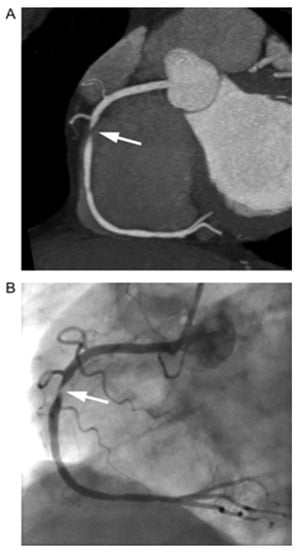

| Schepis et al. [33] | April 2010 | 70 -100 individual NCP (1 to 3 plaques per patient) | Compare NCP volumes on DSCT vs. IVUS. | -Mean total plaque volume by DSCT was 89 ± 66 mm3 (range 14–400 mm3). -Mean total plaque volume by IVUS was 90 ± 73 mm3 (range 16–409 mm3). The mean difference between DSCT and IVUS was 1 ± 34 mm3 (range −131–85 mm3). -Correlation between two modalities (r = 0.89, p < 0.001) | -Modest agreement between DSCT and IVUS (Bland–Altman limits of agreement −67 to +65 mm3). |